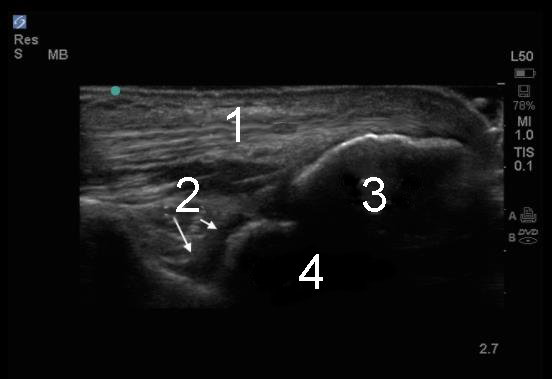

Elbow Posterior Recess Sagittal Image

1. Triceps Tendon

2. Recess

3. Olecranon Process

4. Posterior Trochlea of the Humerus